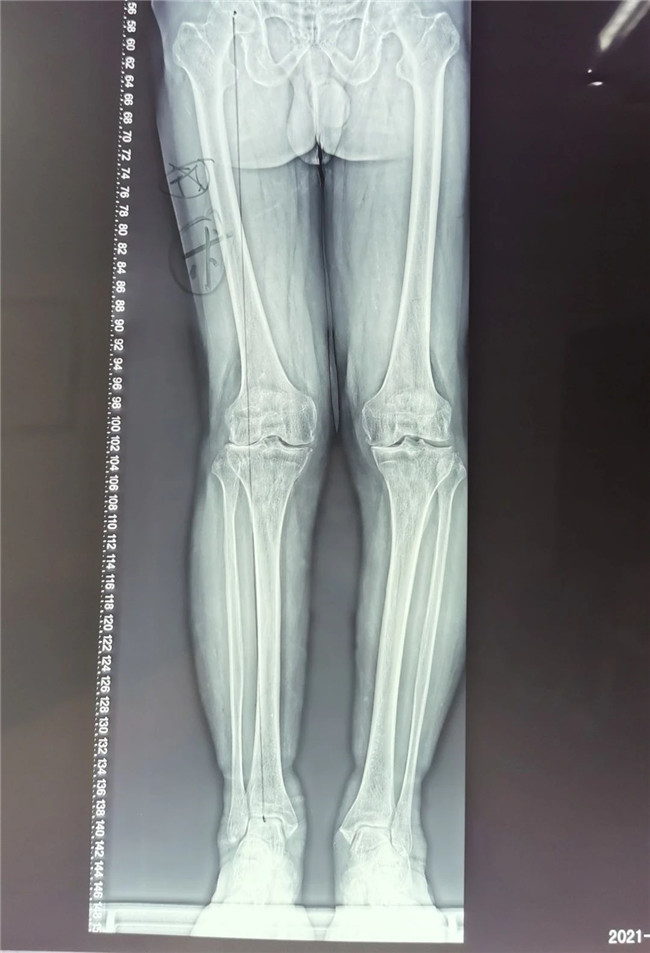

▲右膝關(guān)節(jié)外翻畸形 ▲

75歲的張大爺右膝關(guān)節(jié)疼痛已有數(shù)年,近半年來(lái),右膝疼痛加重,平地行走時(shí)也感覺(jué)困難,疼痛導(dǎo)致右膝不敢完全負(fù)重,走路呈現(xiàn)明顯的跛行姿態(tài)。不堪忍受病痛折磨的病人前來(lái)我院骨科中心找到羅軍主任求醫(yī)。

接診后羅軍主任詳細(xì)檢查病人,發(fā)現(xiàn)病人疼痛癥狀主要集中在膝關(guān)節(jié)外側(cè)間室,右下肢有明顯外翻畸形。這些癥狀都是單髁置換的適應(yīng)癥。雙下肢全長(zhǎng)攝片和右膝內(nèi)翻、外翻位攝片顯示,膝關(guān)節(jié)外側(cè)間隙消失,膝外翻畸形,果不其然印證了上述臨床表現(xiàn)。收治入院后,羅主任團(tuán)隊(duì)決定為患者實(shí)施微創(chuàng)膝關(guān)節(jié)外側(cè)單髁置換術(shù),盡全力為張大爺解除病痛的折磨。